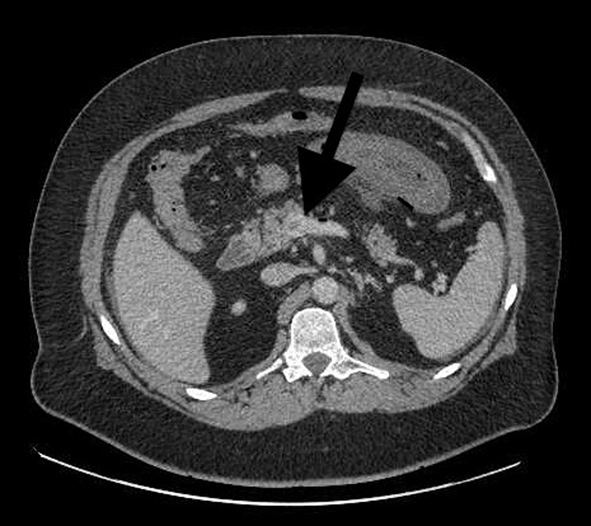

A 40-year-old patient underwent a laparoscopic sleeve gastrectomy for the treatment of obesity (BMI 41 kg/m2, decision validated upon multidisciplinary meeting). The patient was an active smoker, had a paired sleep apnea syndrome and a treated depressive disorder. The surgical procedure was simple with an operative time of 60 min. The immediate postoperative course was simple and uneventful, and the hospitalization ended on the fifth day. One month later, the patient was asymptomatic and lost 15 kg. The patient was again admitted to emergency on the 40th postoperative day for mild abdominal pain associated with nausea. The abdomen was soft; the patient was afebrile and not tachycardic. The abdomen without preparation found some dilated bowel loops. Biology found a moderate leukocytosis without other abnormalities. The computed tomography (CT) found a thrombosis of the superior mesenteric vein associated to a thickened jejunal loop (Fig. 1). The patient was not left empty stomach. The treatment consisted of intravenous heparin therapy that had a favorable result and a week of hospitalization with the administration of antivitamin K. The etiologiy, made after the introduction of heparin therapy, was negative. The patient was advised to stop smoking. Three months later, the patient was asymptomatic still under antivitamin K. A CT scan control is provided on the sixth postoperative month.

![]() Click for large image | Figure 1. Abdominal CT scan with injected on admission (case 1). Arrow: a thrombosis of the superior mesenteric vein. |

The clinical signs of mesenteric venous ischemia are variable and nonspecific. In the presence of abdominal pain of unknown etiology, we shall know how to suggest the diagnosis of a portal vein thrombosis. In case of intestinal ischemia, pain, which is always present, contrasts the absence of physical signs [7, 8]. It can be associated with nausea, vomiting, diarrhea, high or low gastrointestinal hemorrhage [9]. The presumptive diagnosis is often that of perforated ulcer, or acute pancreatitis [10]. Biology shows leukocytosis in half of patients and elevated lactate in one-third of patients [9]. The hyperleukocytosis was present in the two cases. In obese patients the reference radiological examination is the CT with vascular injection [11, 12]. In cases of venous thrombosis, it highlights an endovenous hypodense image that does not show contrast (luminal defect related to the presence of the clot) and a thickening of the walls of the small intestine (Fig. 1) [13].